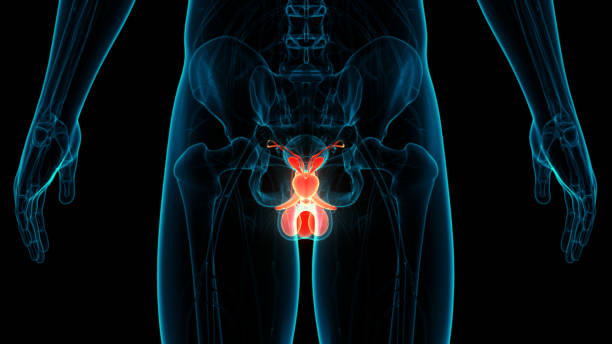

전립선암은 초기에는 증상이 거의 나타나지 않아 발견이 어렵습니다. 하지만 조기에 검진하여 발견된 전립선암의 경우 치료 가능성이 높아집니다. 따라서 전립선암 초기 증상을 알아두고, 정기적인 검진을 받아야 합니다. 이는 특히 합병증 예방을 위해 보다 중요한데 립선암은 진행되면서 합병증을 일으킬 가능성이 있습니다. 예를 들어, 골다공증, 방광 기능 장애, 성기능 장애 등이 그 예입니다. 따라서 초기에 전립선암을 발견하여 합병증 예방을 위한 조치를 취할 필요가 있어 이번 시간에는 전립선암 초기증상에 대해 자세히 알아보겠습니다.

전립선은 방광 주위에 위치하여 방광의 출구를 둘러싸고 있습니다. 전립선암이 발생하면 종양이 전립선을 압박하여 방광의 기능을 저해할 수 있습니다. 이로 인해 방광이 완전히 비어지지 않고 남아있을 수 있어 소변을 제대로 제어하기 어려울 수 있습니다. 이로 인해 요실금이나 배뇨 중 통증을 경험할 수 있습니다.

전립선은 방광과 직접적으로 인접해 있으므로, 전립선암 초기에는 방광에 영향을 미칠 수 있습니다. 이로 인해 방광 불안정이 나타날 수 있으며, 방광 축농증이 진행될 경우 방광 경련과 배뇨 어려움 등이 나타날 수 있습니다.

전립선은 방광과 직접적으로 인접해 있으며, 전립선암 초기에는 전립선의 세포가 방광으로 침범하여 방광 축농증이 나타날 수 있습니다. 이로 인해 배뇨 어려움과 방광에 담긴 소변의 양이 적어지는 등의 증상이 나타날 수 있습니다.